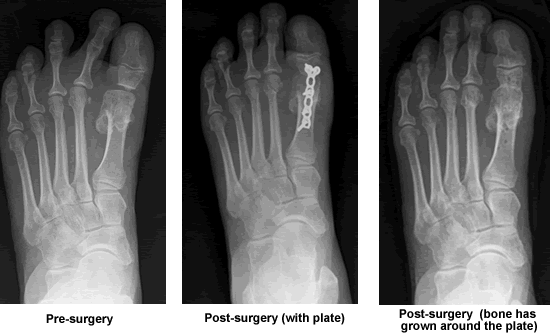

During my first appointment with Dr. Leavitt he ordered x-rays immediately. The radiology lab paged Dr. Leavitt when they were ready to take the pictures and within minutes he arrived to hold my foot in the position he wanted while the x-ray was taken. My foot was badly damaged and much of the bone in the large toe joint was missing and the flexor tendon had been severed. I needed toe separators and bandages every day before I could put on a shoe. My walking time was very limited and the pain was becoming very severe.

Dr. Leavitt and I discussed what needed to be done while viewing x-rays. I did need another surgery. I had few choices. Bones had to be broken, toes had to be fused and no implants were possible. Over the next few weeks, I met another podiatrist who would assist Dr. Leavitt with my surgery and I also met the person who was to make the plate for my foot. Dr. Leavitt was always kind, compassionate, very caring and honest. He told me "this is a big deal" and he was right. Before and after my surgery he answered all my phone calls and e-mails and he always took time to listen. On one occasion, I had to see an assisting doctor while Dr. Leavitt was on vacation with his family. The assisting doctor phoned Dr. Leavitt, who answered the phone call during my visit. I thought, what a very special person this Dr. Leavitt is and how fortunate I was to be his patient. Surgery was done in December 2008, and after three months I was walking without pain on my new left foot.